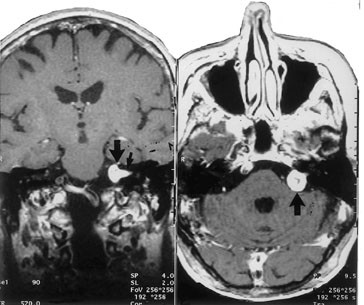

Akustikusnevrinom utgår fra nervus vestibularis og representerer omkring 10 % av alle intrakraniale svulster og 90 % av svulstene i den cerebellopontine vinkel (fig 1).